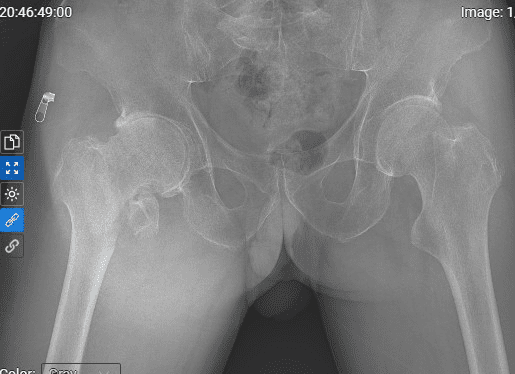

Hình ảnh háng phải của bệnh nhân trước và sau thay khớp toàn phần

Trường hợp bệnh nhân Phạm Th. C (46 tuổi- phường Hải Hòa- TP Móng Cái) do bị viêm khớp háng phải- tiêu chỏm xương đùi 2 bên. Bệnh nhân được phẫu thuật thay khớp háng nhân tạo toàn phần. Sau phẫu thuật, sức khỏe bệnh nhân ổn định, đi lại vận động bình thường.